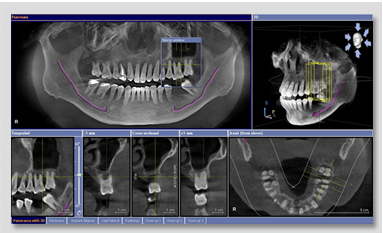

本院引進德國西門子3D數位電腦斷層掃瞄儀「GALILEOS 3D」,為患者的健康把關。電腦斷層又稱 CT,為 Computerized Tomography 的縮寫,意指經過電腦的處理所現出來的影像「電腦斷層攝影術」。透過電腦斷層,可以進一步瞭解患者的口腔狀況,包括︰是否有牙周問題、牙齒有幾顆、有沒有水平智齒、根管治療(抽神經)的狀況,乃至於瞭解患者的口內骨頭狀況,看到下顎齒槽神經叢,藉以選擇更適當直徑、長度的植體,才不會壓迫到神經或根尖骨頭穿孔的後遺診,對患者的安全做妥善的保護。

透過立體電腦影像模擬輔助植牙,可清楚看到3D立體影像,利用不同解剖面,檢查齒槽骨內部的問題,協助植牙醫師,掌握足夠的診斷訊息,包括患者的牙床的形狀、厚度及神經、鼻竇與血管的位置,避免人工牙根可能帶來的風險。在使用上,一般14秒即可完成拍攝,節省時間,且能大面積清楚顯像。此外,該機種是市面上眾多電腦斷層掃瞄中,X光劑量較低的機種之一。

透過3D立體影像,可全方位瞭解患者的口內狀況、骨質結構、神經管走勢等,為患者安全做有效的把關。

3D立體影像透過俯視圖得知根管數量並搭配可變更切片角度的影像,準確得知不同根管的長度。